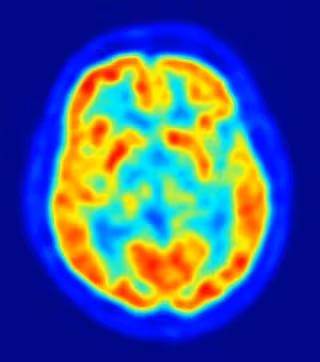

El nacimiento de nuevas neuronas en el cerebro adulto agudiza la memoria en roedores, pero si lo mismo puede decirse de los seres humanos ha sido objeto de debate. Un estudio publicado en la edición de este jueves de la revista 'Cell' revela que más de un tercio de las neuronas se renuevan periódicamente durante toda la vida en el hipocampo, una región importante del cerebro para la memoria y el aprendizaje, se generan en los seres humanos adultos.

Mediante la medición de la concentración de carbono-14 en el ADN de las neuronas del hipocampo de humanos fallecidos, los científicos encontraron que más de un tercio de estas células se renuevan periódicamente durante toda la vida. De esta forma, cerca de 1.400 neuronas nuevas se añaden cada día durante la edad adulta y esta tasa decae modestamente con la edad.